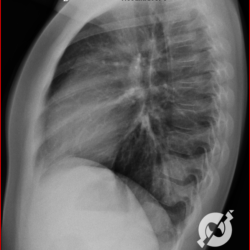

E o nome dado a esta alteração radiográfica que corresponde à substituição do ar alveolar por líquido é a consolidação alveolar.

Uma consolidação alveolar é, por definição, uma opacidade (imagem densa, branquinha) homogênea ou às vezes heterogênea (pela presença de calcificações ou cavidades), de limites mal definidos, exceto quando toca a pleura da parede ou das cissuras pulmonares. É um termo usado tanto em radiografia, como em tomografia computadorizada. Na tomografia, um outro termo é usado: vidro fosco, que é uma opacidade (branquinha mas não tanto como a consolidação), que borra o pulmão mas deixa ver os vasos de permeio (igual bigode de adolescente: dá pra ver todo o fundo).

Nós vamos mostrar aqui um pequeno apanhado de pneumonias de variados agentes, em diversos segmentos e lobos pulmonares, com extensões variadas. O objetivo é identificar o padrão radiológico de consolidação alveolar e não determinar o agente infeccioso, isso vai ser assunto para mais adiante. Aliás já antecipo que é fundamental saber localizar a lesão, porque alguns destes bichos gostam de determinados segmentos, alguns tumores também têm as suas preferências, então localização é fundamental. Se localização não fosse importante, um apartamento na beira do mar sairia o mesmo preço de um apartamento de frente pra BR-101, concordam?

Seguem alguns dos nossos casos de pneumonia para vocês treinarem os olhos e não se apavorarem nos plantões.